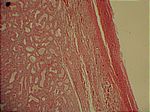

Basedow-Struma, HE